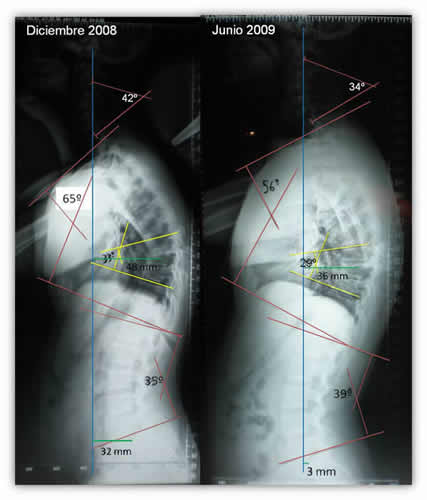

Aumento del Dorso Curvo

- Paciente: R.C. 23 años. Masculino

- Motivo de consulta: Morfológico.

- Diagnóstico Médico: Fractura por aplastamiento de cuerpos vertebrales D8 – D9 y D10. Aumento del Dorso curvo. Derivación médica para tratamiento de RPG.

- Inicio de tratamiento: 23 de mayo 2008. Durante el año 2008 realizó 22 sesiones con una frecuencia semanal. Interrumpe el tratamiento 3 meses. Reinicia las sesiones el 18 de marzo de 2009. En el año 2009 y hasta el momento de la nueva RX realizó 9 sesiones.